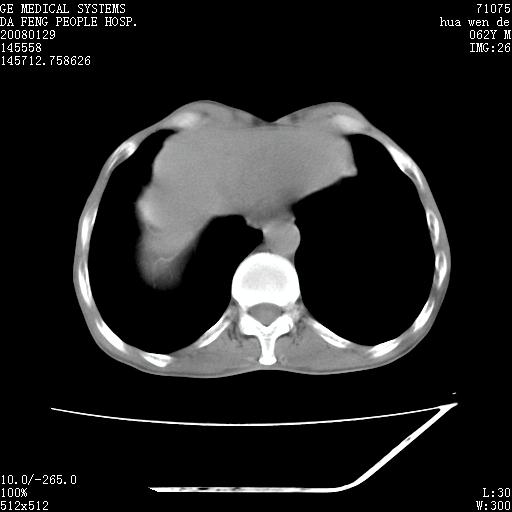

男性,67岁。作肺部检查时发现

右肺脓肿 胸腔胃

考虑:胸腔胃并支气管瘘(并发肺炎,肺脓肿形成)。

理由:1、右上肺内病灶,空洞形成,有液平。

2、肺内多处炎症。

3、前段肺内炎症,支气管引流通畅,与肿块无关系。

考虑:胸腔胃并支气管瘘(并发吸入肺炎,肺脓肿形成)。

1.整个食管扩张,未见明显占位性病变,贲门区亦未见明显占位病变,考虑:贲门失驰缓症;

2.右上肺病变边缘可见毛刺,囊壁厚度不均匀,周围境界较清楚,未见炎性渗出性影,右上肺外带可见片状影,边缘不清,考虑:肺癌伴空洞形成、右上肺炎。

食管全程扩张,壁均匀不厚,喷门失弛缓症

右上肺空洞可见液平,临近肺野磨玻璃密度,考虑1.结核2.脓肿